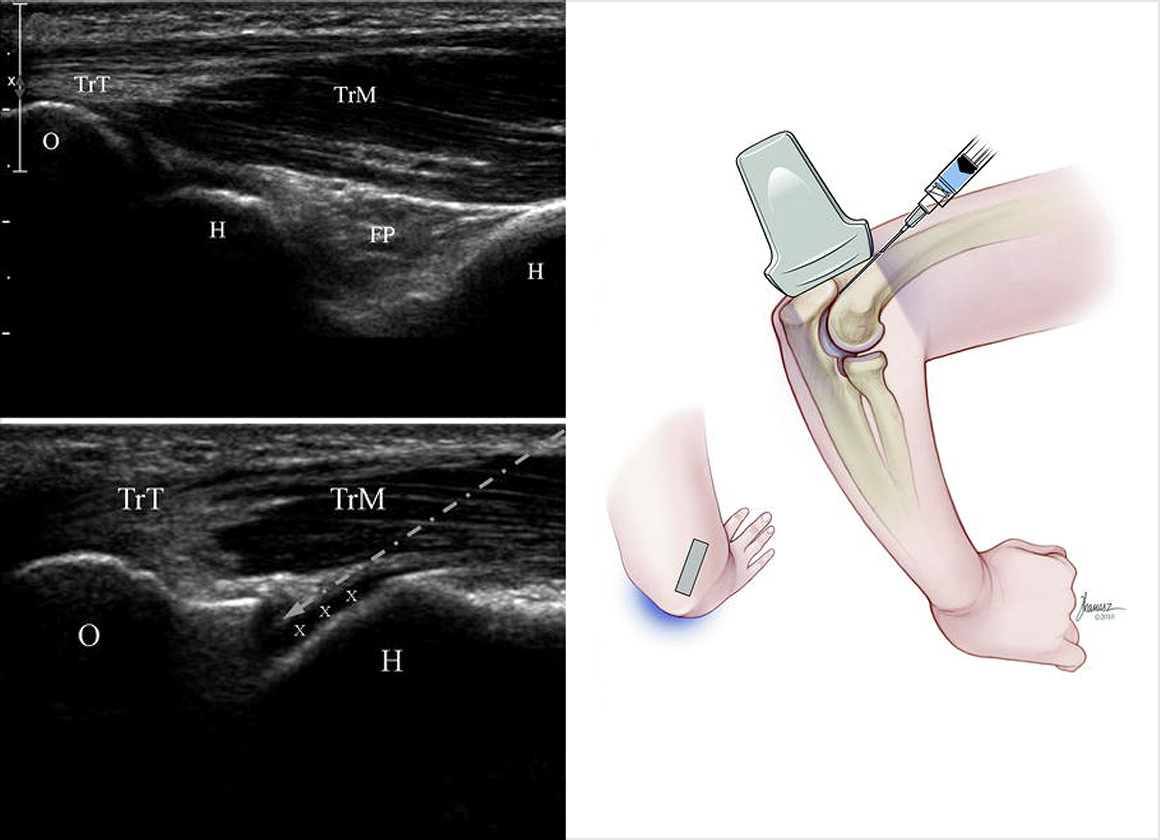

초음파 영상을 보며 원하는 부위에 정확히 약물을 주입하며 팔꿈치, 손목, 발목 등 많이 사용하고 손상되기 쉬운 다양한 관절에 효과가 있습니다.

초음파 영상을 통해 병변의 진단과 함께 인대나 힘줄의 손상부위, 어깨나 무릎 등의 관절강 내 정확한 위치로 주사 치료를 시행합니다.